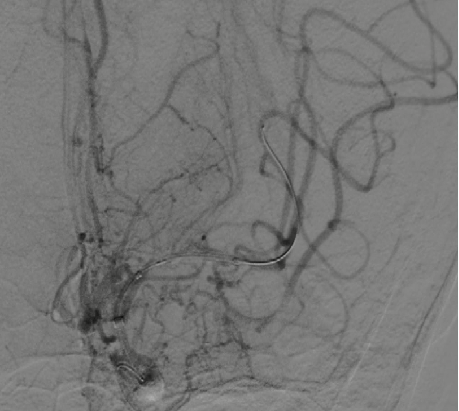

导引导管到位,导丝通过病变。

导丝怎么扩【载药时代 球扩天下】NOVA DES®颅内药物洗脱支架在颅内富穿支区域使用体会二例!_https://www.jmylbn.com_新闻资讯_第31张

支架释放后影像。